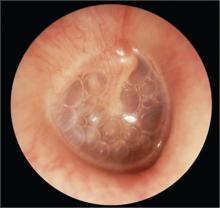

Air-fluid levels in ear

A 2-year-old child was brought in for a well-child exam 2 months after an episode of acute otitis media. He appeared healthy and was meeting all of his developmental milestones. An otoscopic examination revealed air–fluid levels in the right ear.

The family physician (FP) diagnosed otitis media with effusion (OME) in this patient.

Common otoscopic findings for OME include: air–fluid level or bubbles or a cloudy tympanic membrane (TM). Redness of the TM may also be present. Physicians should use pneumatic otoscopy as the primary diagnostic method for OME. Impaired mobility of the TM is the hallmark.